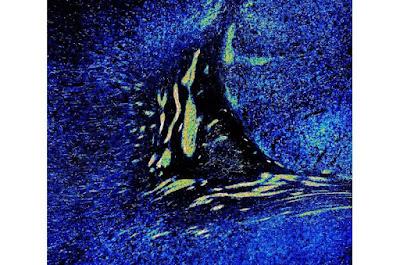

Una investigación de Shawn Sorrells, de la Universidad de Pittsburgh publicada en la revista Nature, revela que una extensa migración neuronal continúa en el cerebro después del nacimiento, contribuyendo al desarrollo de funciones cerebrales esenciales como el aprendizaje y la memoria.

El estudio indica que la migración neuronal posnatal en la corteza puede sustentar períodos críticos de neuroplasticidad, haciendo que el cerebro sea particularmente receptivo a los cambios y adaptaciones.

La investigación sugiere que la extensa migración neuronal posnatal en la corteza podría ofrecer una explicación de la vulnerabilidad de las neuronas a la neurodegeneración. Este hallazgo tiene importancia en el contexto de enfermedades neurodegenerativas como el Alzheimer.

La investigación contradice la creencia anterior de que la migración neuronal cesa en gran medida después del nacimiento, destacando la extensa y continua migración y duración dentro de las regiones del cerebro que controlan los pensamientos y las emociones. Explica el mecanismo a través del cual el cerebro humano produce miles de millones de nuevas neuronas y continúa reclutando neuronas hasta bien entrada la infancia.